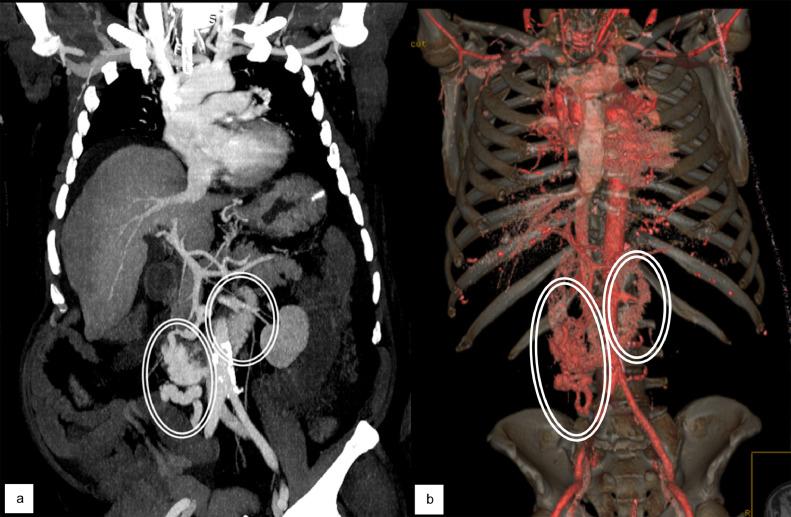

Duodenal varices are ectopic varices that can cause severe and life-threatening gastrointestinal bleeding. Diagnosis and treatment of ectopic varices is challenging, because endoscopy is often unproductive in detecting and treating ectopic varices. Interventional radiology appears as an alternative in this setting, thanks to its important role in treating the bleeding caused by ectopic varices and in preventing rebleedings. We present an interesting case of bleeding ectopic varices in a male 62-years-old cirrhotic patient (Child-Pugh B8). The patient presented with hemorrhagic shock caused by massive melena. CT angiography showed intraluminal blood and identified the source of bleeding as an ectopic varicose vein draining into the superior mesenteric vein. Interventional radiology approach was the only applicable one to reach and effectively treat the source and cause of bleeding by TIPS placement and embolization of the collateral feeding at the same session.

十二指肠静脉曲张是一种异位静脉曲张,可导致严重且危及生命的胃肠道出血。异位静脉曲张的诊断和治疗具有挑战性,因为内镜检查在检测和治疗异位静脉曲张方面往往效果不佳。在这种情况下,介入放射学似乎是一种替代方法,这得益于其在治疗异位静脉曲张引起的出血以及预防再出血方面的重要作用。我们报告了一例有趣的病例,一名62岁的男性肝硬化患者(Child-Pugh B8级)出现出血性异位静脉曲张。患者因大量黑便导致失血性休克。CT血管造影显示管腔内有血液,并确定出血源为一条汇入肠系膜上静脉的异位曲张静脉。介入放射学方法是唯一适用的方法,可通过在同一次手术中放置经颈静脉肝内门体分流术(TIPS)和栓塞侧支供血来有效到达并治疗出血源及病因。